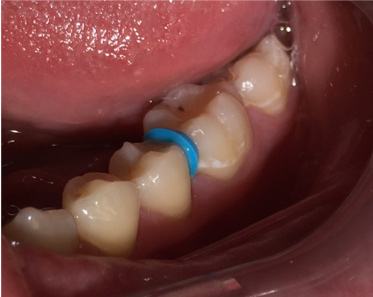

A 28-year-old woman, who previously had braces, had circumferential gumline decalcification (Figure 1) and wished to arrest lesions before they worsened (bitewing, Figure 2). The following protocol is consistent with the product instructions for the resin infiltration material from DMG America, which is the only commercially available resin infiltration system in the US.

2. Place a separator to create room between the teeth (Figure 1). This can be done up to 1 week in advance of treatment.

Fig 1.  Circumferential gumline decalcification (Fig 1) and bitewing (Fig 2) of a 28-year-old woman.

Figure 1